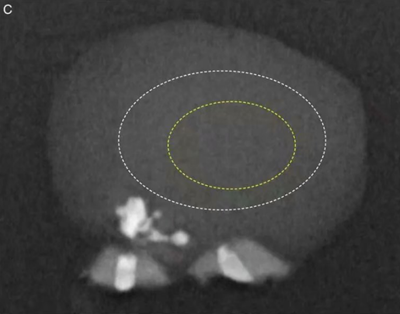

圖9. 對切片進(jìn)行分析后得到的放線菌菌落(黃線)和周圍炎癥(白線)范圍的示意圖。